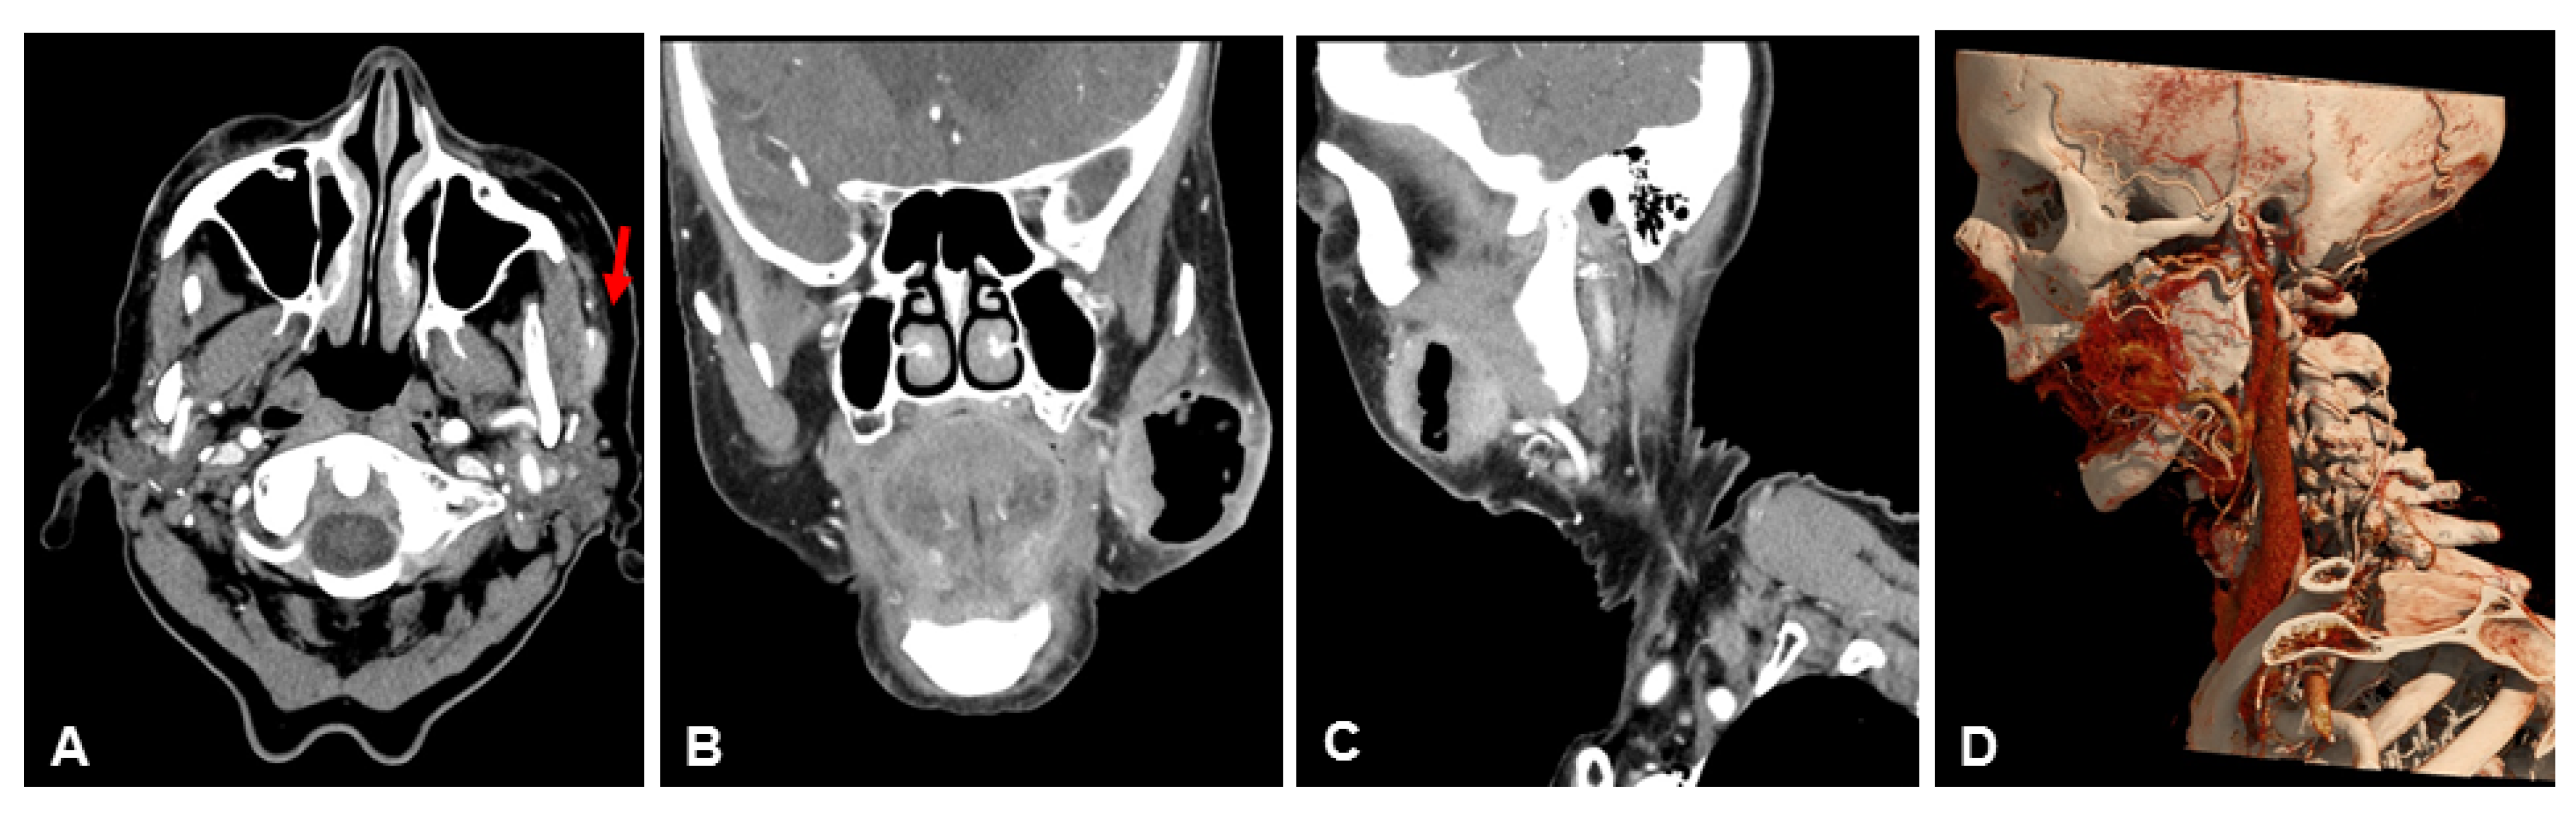

3.2. Subjective Image Quality